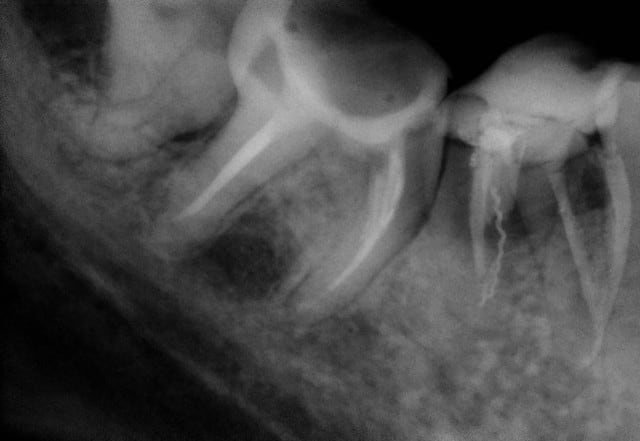

J'ai déjà récupéré de nombreuses racines à ce stade et les ai utilisées comme piliers de bridges ou les ai couronnées, dans la mesure ou l'ancrage alvéolaire était solide et en respectant les furcations pour y assurer l'hygiène.

La gencive lasérisée devient très ferme avec le temps et le déchaussement se stabilise. Ces restaurations se comportent bien sur un recul de plusieurs années.

Un exemple: une 46 avec furcation linguale dénudée après lasérisation et restauration par une endocouronne céromère réalisée il y a 9 ans et sans signe clinique avec une excellente attache gingivale malgré la perte osseuse, les 3 avant dernières images ont été prises lors d'un contrôle en mars dernier ...

9 années pour cette patiente de 90 ans, cela vaut bien le coup d'essayer vous ne croyez-pas? (dernière radio)

Avec le laser, on devient bien plus conservateur...